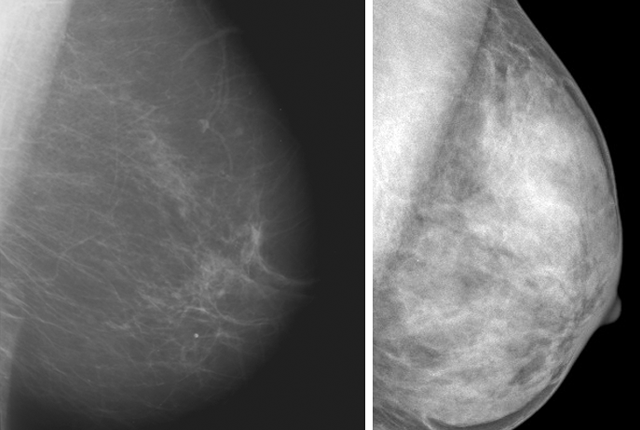

He explained that radiologists subjectively review mammograms to characterize breast tissue into one of four categories, which range from almost entirely fatty to extremely dense with fibroglandular tissue (see accompanying chart).

It’s important to note, Lee said, that half of all women are classified as having dense breasts just by the nature of the categories.